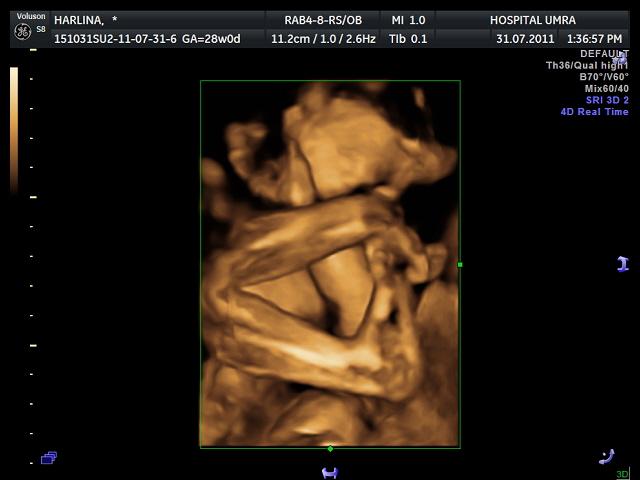

finally he revealed himself after more than 30 minutes!! penat doc dok goncang-goncang perut aku just to force him to move.. still part of his feet is covering his face.. degil kan baby M~

special pose for mummy and daddy.. ACTION KAMIN!!! tangan bersilang.. kaki pun naik sampai kat muka, mmg flexible sungguh la budak kenit nih~

eh gatal pulak kaki ni.. kejap ye saya garuk!! krukk krukk~~

p/s: baby M ni super flexible and degil.. tangan and kaki dua-dua duduk depan muka, bila kene poke dia boleh buat dek jek.. ikut perangai sapa la tuh?? tapi aku still happy~~ tak sabar nak jumpa baby M!